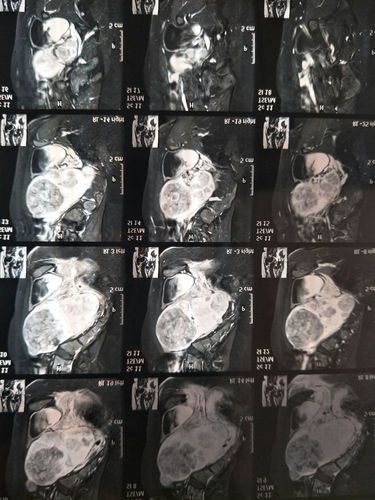

术前的磁共振显示的子宫内的多发肌瘤